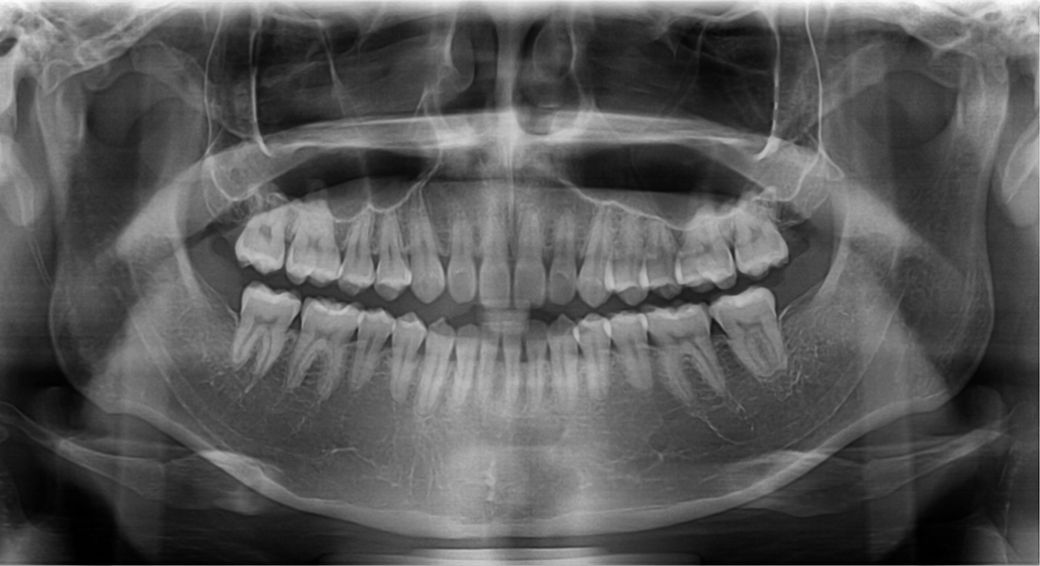

돌출입 교정 상담 받았는데 치과에서 앞니 치근이 짧다고 발치 교정은 추천하지 않으며 또한

비발치 전체 교정으로 사랑니 공간으로 치아전체 후방이동 또한 무리일 것 같다고 합니다

앞니 1개의 치아 뿌리가 다른 것보다 짧습니다. 이런 경우 교정을 하면서 치아에 힘을 주면 치아 뿌리가 더 짧아지는 치근흡수가

일어날 가능성이 있습니다. 그러나 꼭 교정을 하시고 싶으면 교정하는 것도 큰 무리가 아닐 수도 있습니다. 양악수술은 큰 수술이며

현재 상악 전치와 하악 전치의 뿌리의 길이가 정상적인 것보다 짧기 때문에 무리하게 후방견인을 하다가 치아 뿌리가 더 짧아지게 되면 나중에 잇몸뼈의 높이가 낮아지게 되었을 경우에 조기에 상실할수 있는 가능성이 있습니다.